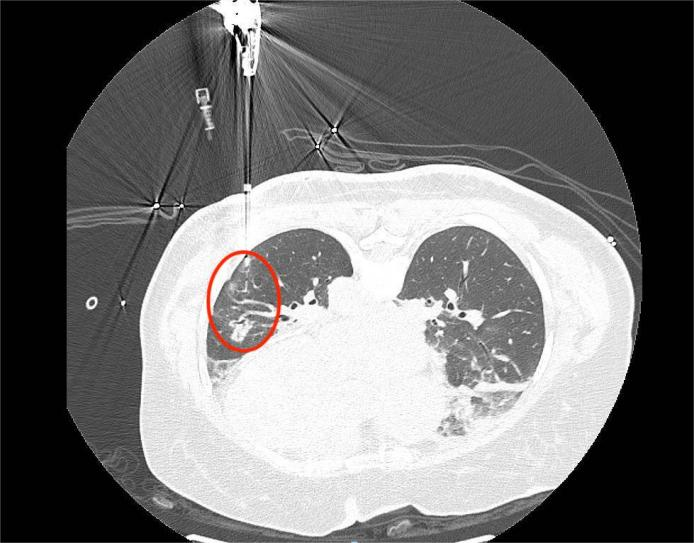

▲术前CT

患者手术指征较明确,因其合并有其他基础病,于是在围术期前期给予降压、控制血糖、抗凝等治疗。综合考虑患者病灶部位、手术耐受性、合并多种基础病等原因,在经过多学科联合会诊讨论后为患者制定了个性化的手术治疗方案,最后由唐中明主任与主管医师危云辉在CT引导下行经皮左下肺结节微波消融术+左下肺结节穿刺活检术,术后病理提示为肺腺癌。